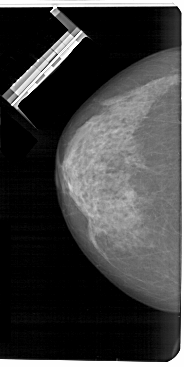

A_1465_1.LEFT_CC

LEFT_CC LINES 5491 PIXELS_PER_LINE 2746 BITS_PER_PIXEL 12 RESOLUTION 43.5 NON_OVERLAY